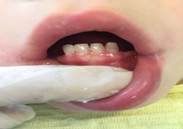

Figuras 11, 12 y 13: Aspectos clínicos de la cavidad bucal con la prótesis removible superior e inferior en boca. Instalación

El paciente retornó para su control odontológico preventivo en forma periódica, y a los tres meses de la colocación de las prótesis, para continuar con el control de la infección y control de los mantenedores de espacio (Figura 14).